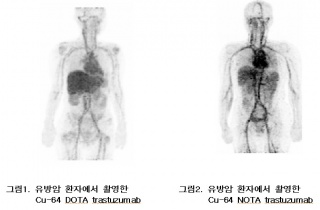

Á¶Á÷°Ë»ç °íÅë ¾øÀÌ À¯¹æ¾Ï Á¤¹ÐÁø´Ü °¡´É¼º

¹æ»ç¼ºÀǾàǰ°ú PET/CT¸¦ Ȱ¿ëÇØ À¯¹æ¾Ï Á¤¹ÐÁø´ÜÀÌ °¡´ÉÇØÁú °ÍÀ¸·Î º¸ÀδÙ. 6ÀÏ Çѱ¹¿øÀÚ·ÂÀÇÇпø À¯¹æ¾Ï ¿¬±¸ÆÀ(¿Ü°ú ³ë¿ìö2017-11-06 11:47:05